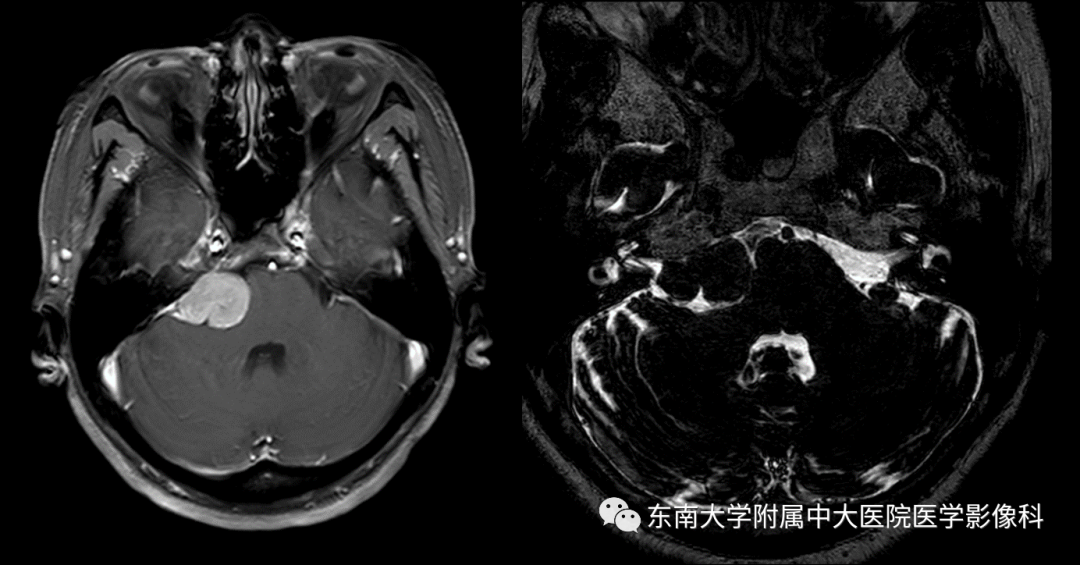

女,67岁,因“右侧嘴角、舌尖部麻木5月余”入院